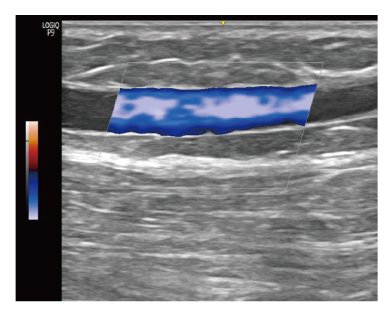

하지정맥류 진단은 혈액의 역류 진단은 육안으로는 다 알 수 없습니다.

혈관 초음파를 통해 발병 부위를 면밀히 관찰해야 합니다.

| 정상 하지정맥 | 역류가 일어난 하지정맥 | |

도플러 초음파 검사라는 혈관 초음파 검사를 통해 고장난 판막의 위치와 역류 시간을 정확하게 파악할수 있는 검사입니다. |